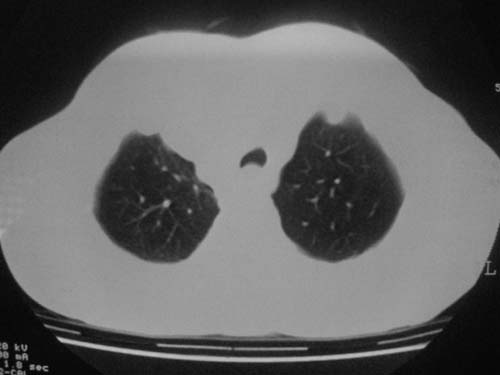

以下是引用科室第一人在2010-3-25 20:30:00的发言:[br]1:纵膈肿瘤性病变,恶性胸腺瘤可能性大伴纵膈右肺门淋巴结转移,右侧胸腔积液。[br]2:右侧肺门肿瘤性病变,纵膈淋巴结转移,右侧胸腔积液。右下叶转移。

以下是引用子期在2010-3-25 21:00:00的发言:[br]先考虑右中央型肺癌伴转移。

以下是引用江广1996在2010-3-25 22:49:00的发言:[br]通常肺癌向纵隔转移多见,纵隔肿瘤向肺内转移少见(有的表现为向肺内侵润)。本例以一元论考虑:右中心型肺癌并纵隔淋巴等多处转移。[br][br][本贴已被 江广1996 于 2010-3-25 22:50:07 修改过]

以下是引用yangyudong333在2010-3-26 6:43:00的发言:[br]“冰冻纵膈”,考虑纵膈淋巴瘤伴肺内及胸膜侵润。